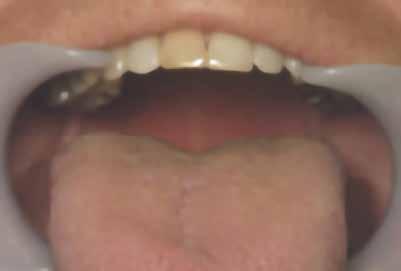

1. ábra: Nyelv helyzete az okkluzális sík felett.

2. ábra: Mallampati besorolás 4, mindegyik minimális orális térfogatot jelez.

angiotenzin II receptor antagonista) 50 mg naponta egyszer, Nexium (protonpumpa-gátló, amely csökkenti a gyomorban termelődő sav mennyiségét) (GERD) 40 mg naponta, Intuniv (multivitamin) 4 mg naponta, és aszpirin 81 mg naponta egyszer. Klinikailag a nyelv az okkluzális sík fölött helyezkedett el, hiperkeratózis (B), a nyelv légutakba való behúzódása és Mallampati 4, amely mind minimális szájüregi térfogatra utalt (1–2. ábra). Ezek indikálták az alvásfogászati készülékes kezelést. Az izomtapintás elhanyagolható volt, és az állkapocs mozgástartománya is normális volt. A maximális nyitás 45 mm volt (1–2. ábra), oldalirányú elmozdulással 12, illetve 10 mm balra és jobbra. Az állkapocs normál mozgástartománya 42–52 mm volt maximális nyitás esetén, emellett oldalirányú elmozdulás 14 mm volt [13]. Az állkapocs ízületeinek dinamikus funkcióértékelését Joint Vibration Analysis (JVA [BioResearch]) segítségével végezték, és a lágy szövetek esetében a normál határokon belülinek, valamint kétoldali porckorongok perforációjának mentesnek találták (3. ábra)